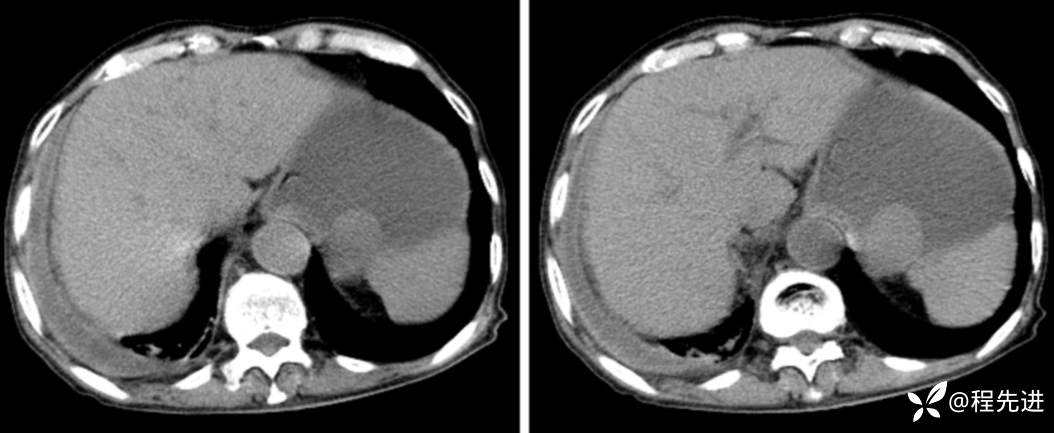

CT

动脉期